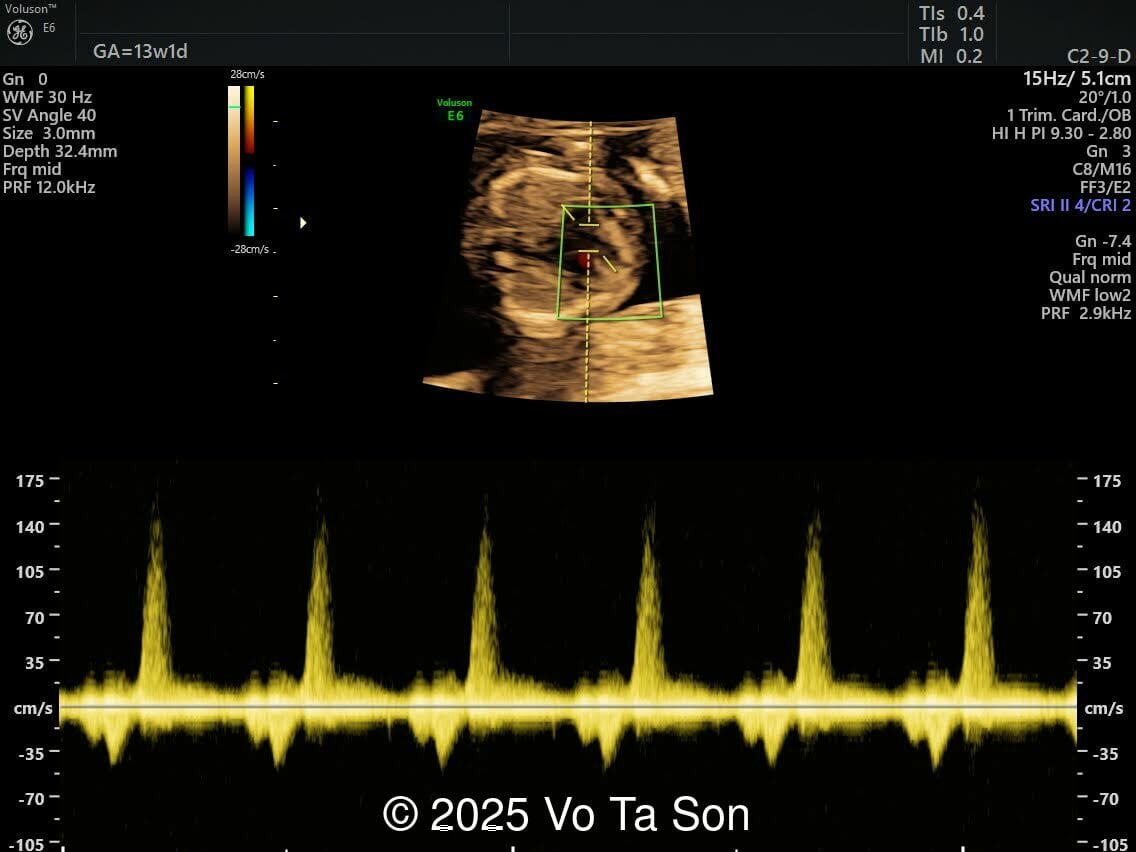

- Ventricular septal defect (VSD)

- Tricuspid valve regurgitation